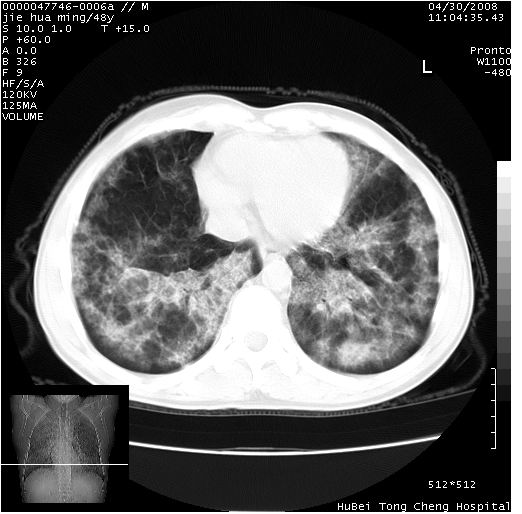

以下是引用dr.yang在2008-5-1 6:25:00的发言:[br]两肺广泛毛玻璃样的片状影,密度不均,边缘欠清,呈碎石路样改变,[br]考虑,1双肺间质性肺炎,2肺泡蛋白沉积症3支气管肺泡癌[br]

以下是引用hhcckk在2008-5-1 8:06:00的发言:[br]支持肺泡蛋白沉积症[br]依据:[br]1、病灶边缘清楚----地图征[br]2、病灶内部小叶间隔或小叶内间隔增厚所形成的网格状影----碎石路样表现[br]3、抗炎治疗无效(炎症抗炎治疗有效)[br]4、纵隔内未见肿大淋巴结(肺泡细胞癌时常有)[br][br]附肺泡蛋白沉积症资料[br][br]肺泡蛋白沉积症(pulmonary alveolar proteinosis)是一种原因不明的以肺泡腔内大量含脂糖蛋白样物质沉积为特征的疾病。[br]病理改变:(1)肺泡和细支气管腔内充满大量含脂糖蛋白样的粘稠物质,该物质为颗粒状或絮状的糖原pas染色阳性的磷脂蛋白。(2)肺泡壁及其间隔无异常改变。胸膜和淋巴结不受累及。(3)晚期可出现弥漫性肺间质纤维化。[br]临床表现:(1)好发年龄30~50岁,男性多于女性,偶见于儿童;(2)主要症状为呼吸困难、咳嗽、低热、消瘦、低氧血症和杵状指等。1/3的患者无症状。(3)实验室检查:痰液或肺泡灌洗液中可找到pas染色阳性颗粒物质。[br]hrct表现:肺泡蛋白沉积症具有特征性改变,即“碎石路样”表现(crazy-paving appearance,cpa)。主要包括(1)斑片状磨玻璃影:指肺野密度朦胧增加,内可见肺血管纹理影,系肺泡腔内充满低密度的磷脂蛋白物质所致。(2)其内部小叶间隔或小叶内间隔增厚所形成的网格状影,为小叶间隔水肿、肺泡壁内淋巴细胞和巨噬细胞浸润以及小叶内淋巴管扩张的缘故。(3)病灶边缘清楚,呈地图样分布于肺野外围或肺门及中央区。[br]

以下是引用zsl6918在2008-5-1 7:35:00的发言:[br]双肺磨玻璃样病变,可见铺碎路石征,病变区与正常区交错。边界清晰。符合肺泡蛋白质沉着征,高分辨扫描会更清楚漂亮。建议临床肺泡灌洗。

以下是引用yangyudong333在2008-5-1 5:36:00的发言:[br][br] 两肺广泛毛玻璃样的片状影,密度不均,边缘欠清,呈碎石路样改变,[br]考虑,1双肺间质性肺炎,2肺泡蛋白沉积症[br]